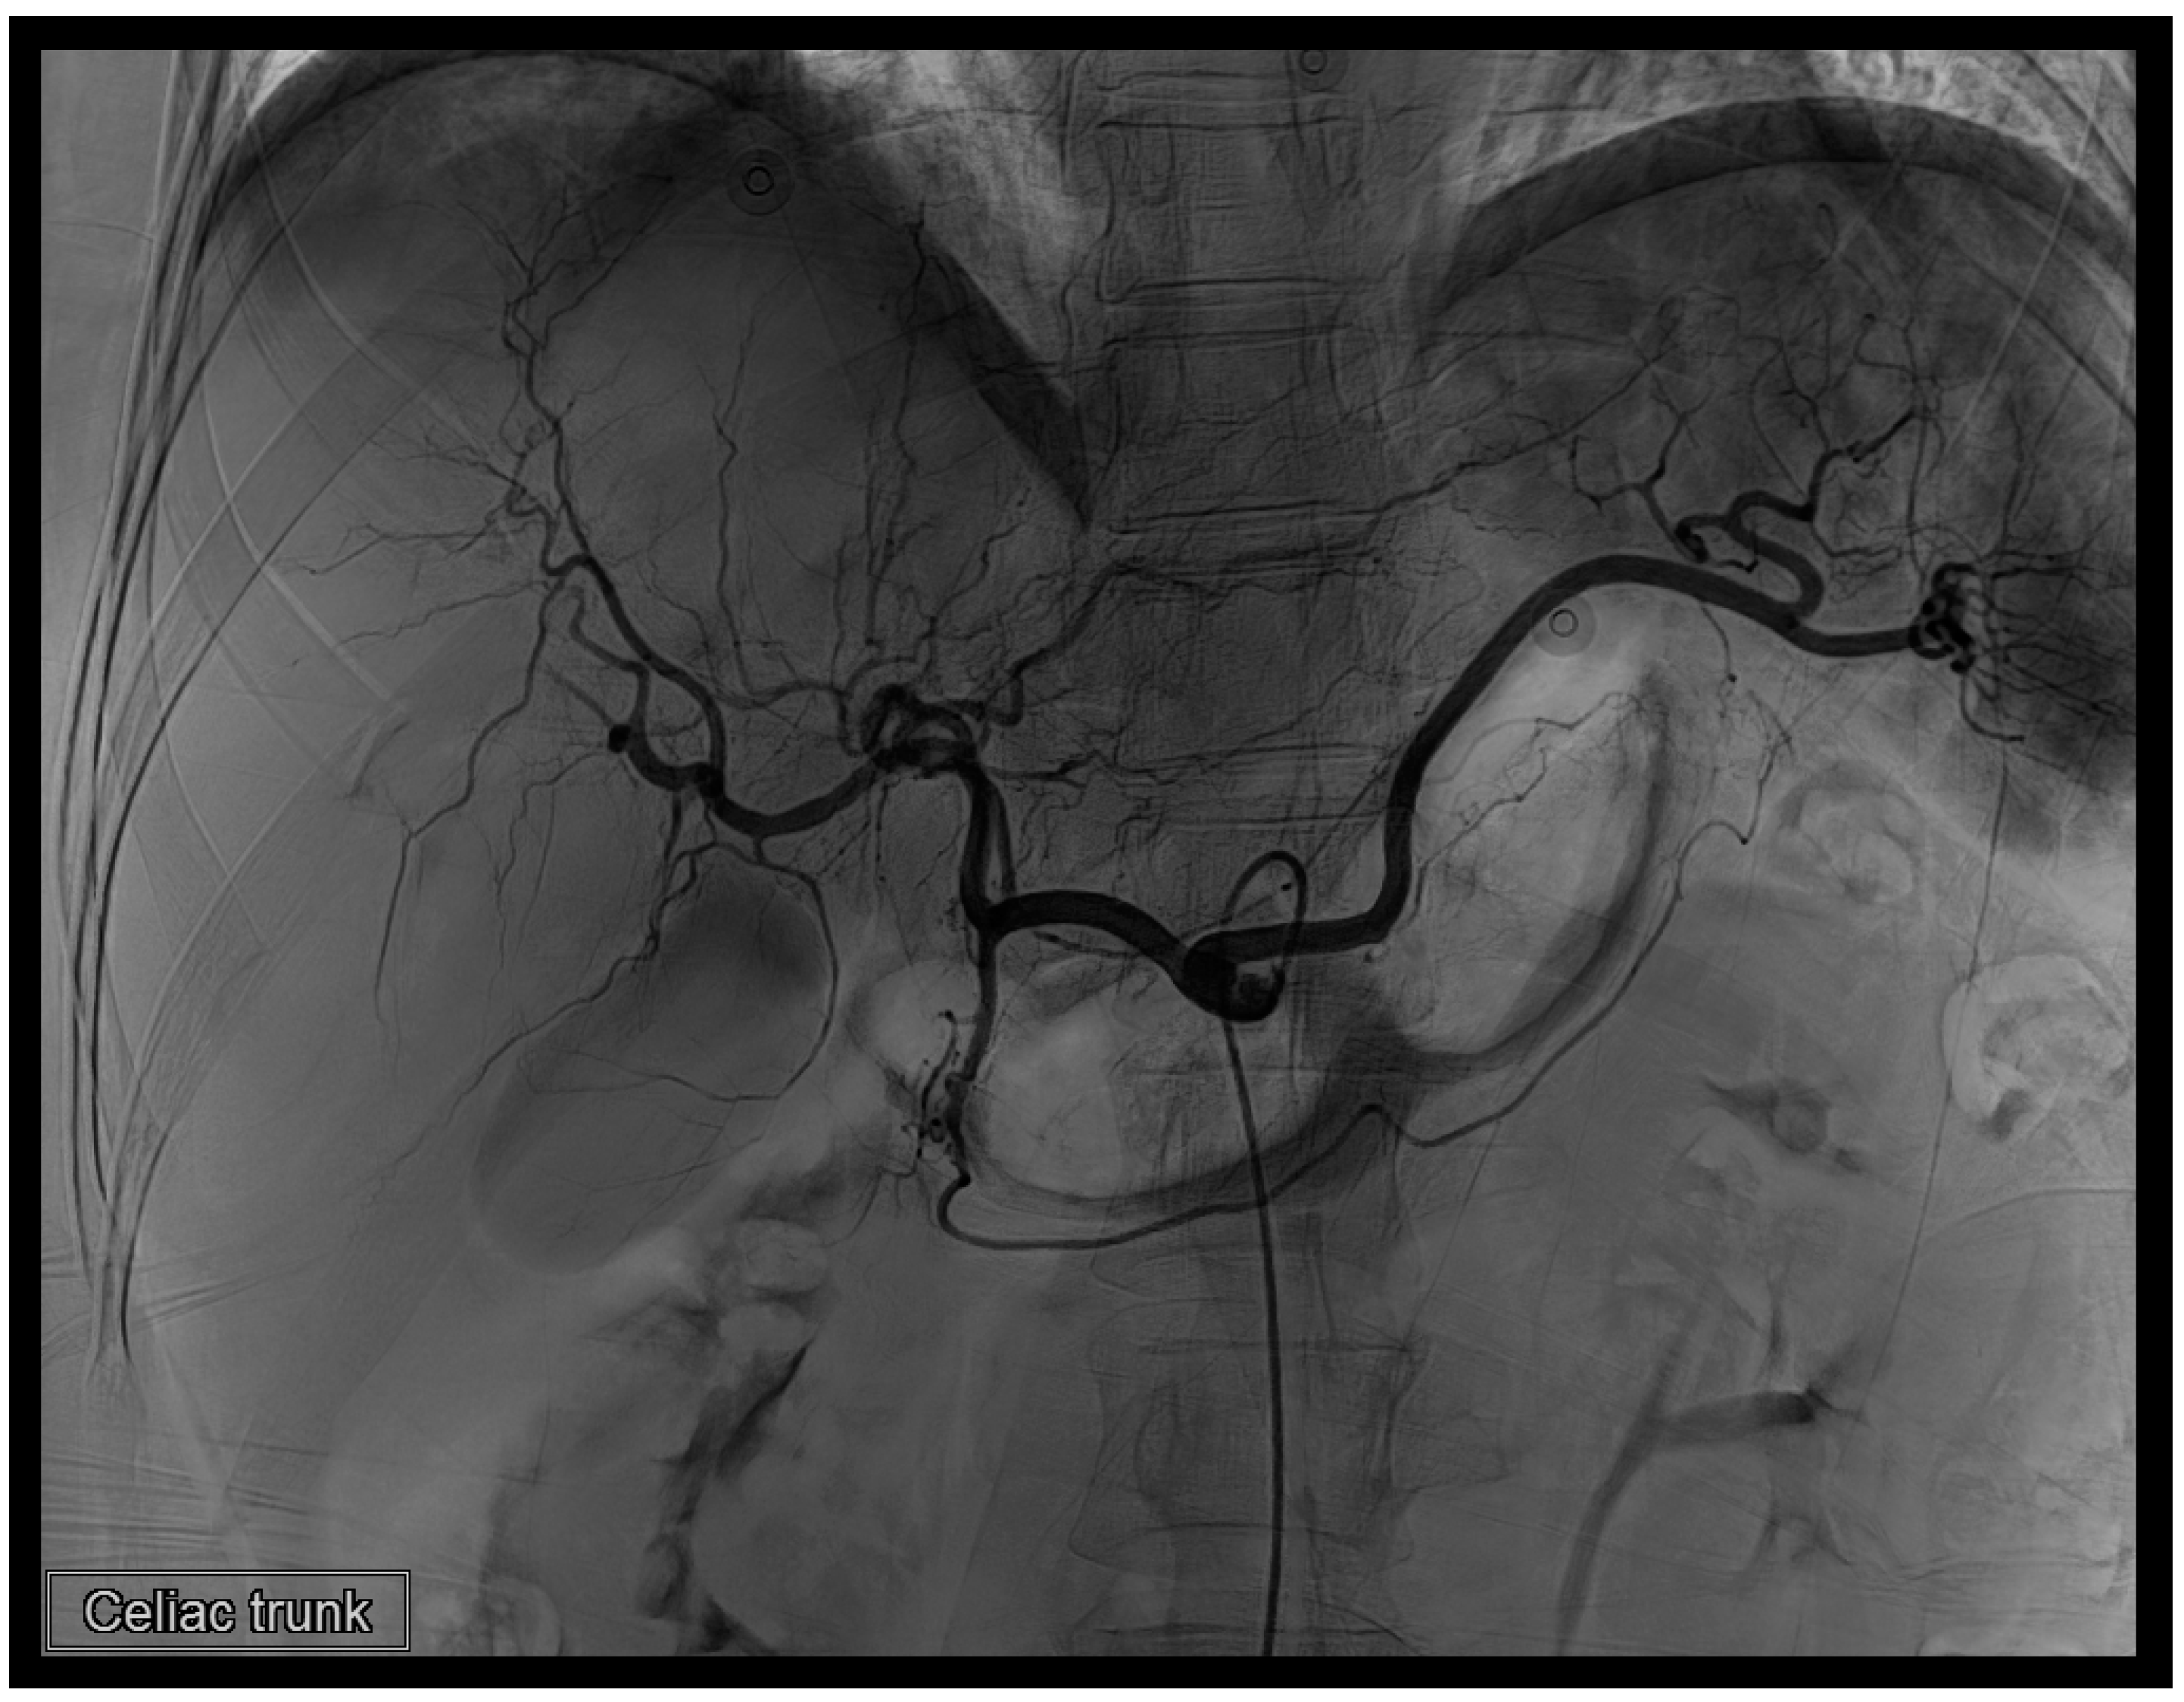

Figure 5. First TAE. Prior to concluding the procedure, we conducted another angiography at the celiac trunk. No evident extravasation was observed in this instance.